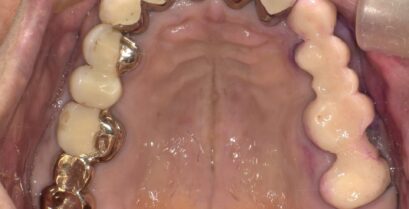

虫歯治療!

皆様こんにちは。 暖冬の今年とはいえやはり寒い。そして夜になれば風が冷たいものです。 そんな時、風で歯がしみる症状はありませんか? 風で歯がしみる。。...